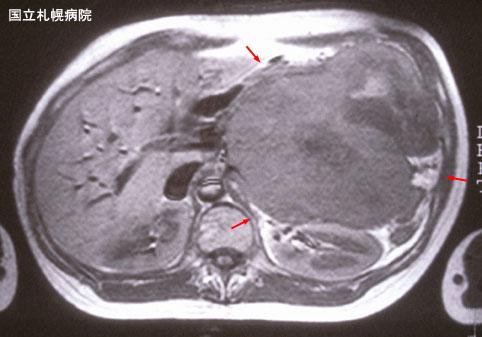

Condrosarcoma Mesenquimal extraóseo intra-abdominal gigante que muestra una severa compresión del estómago (Caso presentado por el Hospital Nacional de Sapporo)

[Image-ID:3271]

Resonancia Magnética

diámetro mayor del tumor

40 -